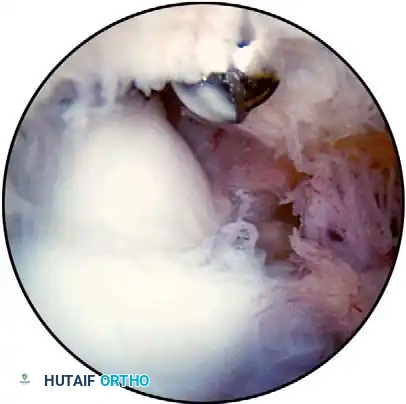

Lateral Portals

The Direct Lateral Portal:

Located in the "lateral soft spot" where elbow effusions are most easily palpable and aspirated. It is situated in the center of the triangle formed by the lateral epicondyle, the radial head, and the tip of the olecranon. Instruments passed through this portal traverse the skin, subcutaneous tissue, anconeus muscle, and joint capsule. This is typically the first portal established to distend the joint.